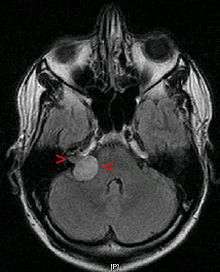

Although there is an inheritable condition called Neurofibromatosis Type 2 (NF2) which can lead to acoustic neuroma formation in some people, most acoustic neuromas occur spontaneously without any evidence of family history (95%).[3] NF2 occurs with a frequency of 1 in 30,000 to 1 in 50,000 births. The hallmark of this disorder is bilateral acoustic neuromas (an acoustic neuroma on both sides) usually developing in late childhood or early adulthood, frequently associated with other brain and spinal chord tumors.

As intracanalicular tumors grow, they tend to expand into the cerebellopontine angle (CPA), leading to their characteristic "ice-cream-cone like" appearance on a radiograph. When the tumor expands extracanalicularly, the growth rate often increases, since it is no longer confined by the bony auditory canal. As the schwannoma expands into the CPA, it may infringe on cranial nerve V (controls facial sensation, chewing and swallowing) and cranial nerve VII (controls facial expression and taste). Cranial nerve VIII, along with these two nerves, also passes through the CPA, so more serious or complete hearing loss and episodes of vertigo may occur as the tumor infringes on it there.

A diagnosis of NF2 related bilateral acoustic neuromas creates the possibility of complete deafness if the tumors are left to grow unchecked. Preventing or treating the complete deafness that may befall individuals with NF2 requires complex decision making. The trend at most academic U.S. medical centers is to recommend treatment for the smallest tumor which has the best chance of preserving hearing. If this goal is successful, then treatment can also be offered for the remaining tumor. If hearing is not preserved at the initial treatment, then usually the second tumor, in the only-hearing ear, is just observed. If it shows continued growth and becomes life-threatening, or if the hearing is lost over time as the tumor grows, then treatment is undertaken. This strategy has the highest chance of preserving hearing for the longest time possible.[10]